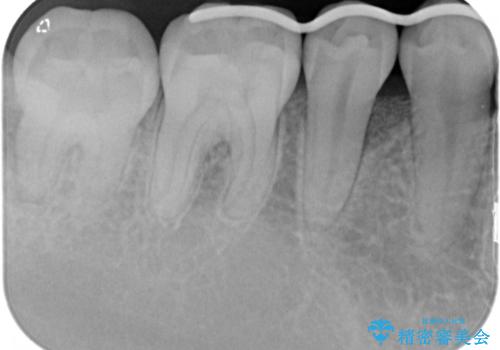

患者様は、他院で右下の歯を抜歯かもと言われました。全体の歯周病はなく、右下の1歯だけ骨が極端に減少していました(初診時歯周ポケット7mm。通常は3mm以下。)。その歯だけ咬合が強いことが原因と考えられたため、咬合を弱くする処置と減少した骨を再生する処置が必要になりました。

骨の再生治療手術をして10か月経過観察をしたのち、骨を平坦化する手術を行い、治療終了となりました。